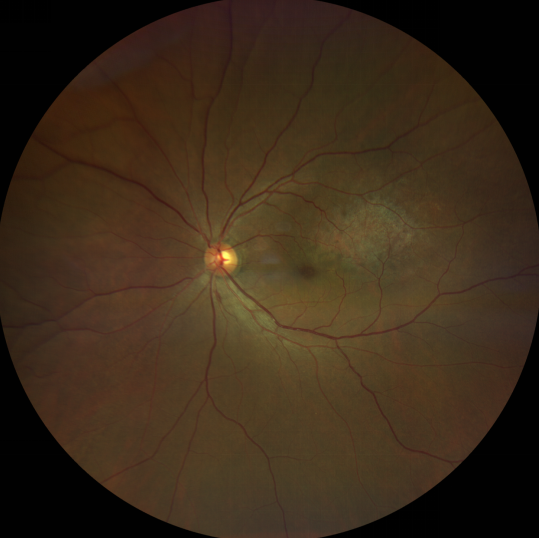

脈絡(luò)膜黑色素瘤患者在發(fā)病早期無眼痛等癥狀,當(dāng)腫瘤較小時(shí)較難發(fā)現(xiàn),隨著病程進(jìn)展,腫瘤增大,發(fā)生滲出性視網(wǎng)膜脫離或累及黃斑,視力下降才就診。

脈絡(luò)膜黑色素瘤惡性程度高,50%的患者會(huì)發(fā)生轉(zhuǎn)移,轉(zhuǎn)移到肝、肺等遠(yuǎn)處臟器,常見的轉(zhuǎn)移方式是經(jīng)鞏膜導(dǎo)管擴(kuò)散,經(jīng)視神經(jīng)蔓延者罕見。一旦發(fā)生轉(zhuǎn)移,1年生存率只有10%,即絕大多數(shù)病人在半年至1年間會(huì)失去生命。因此,早期診斷和選擇合適的治療方式對(duì)有效提高局部腫瘤的控制率、降低腫瘤的遠(yuǎn)處轉(zhuǎn)移率、延長患者的生存率具有重要意義。